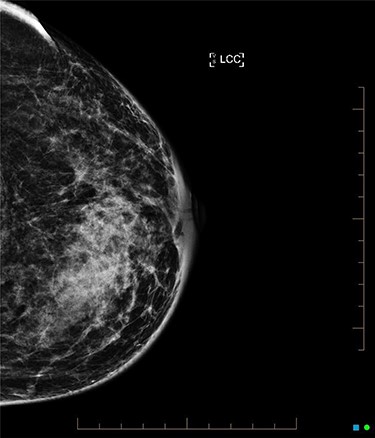

An ultrasound of the left breast demonstrated a 60-mm irregularity with no underlying collection at the 10 O’clock position, 2 cm from the nipple (Fig. 1). AB was treated with 5 days of oral flucloxacillin for presumed mastitis, and underwent a bilateral mammogram and ultrasound due to the suspicious irregularity of the left breast lesion. This showed an area of asymmetric density in the medial left breast with hyperemia (Fig. 2). The right breast showed two clusters of pleomorphic microcalcifications in the upper outer quadrant, further characterized as irregular lesions measuring 16 × 11 × 11 mm and 9 × 10 × 7 mm (Fig. 3).